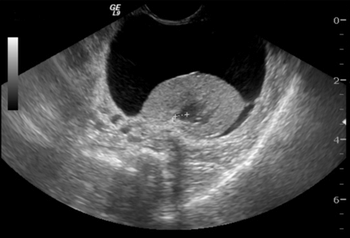

What is the lesion in this abdominal ultrasonogram?

Abdominal ultrasound has taken on a "larger-than-life" position in diagnostic imaging in veterinary medicine for several reasons. First and foremost is that ultrasound is a non-invasive technique that can be used by the small animal practitioner for imaging the peritoneum, parenchyma of the abdominal organs and retroperitoneum.

This brief overview of abdominal ultrasound is meant to be just that – an overview. If you are serious about ultrasound, you will take it upon yourself to review on the ultrasound references in physics such as that by Kremkau.